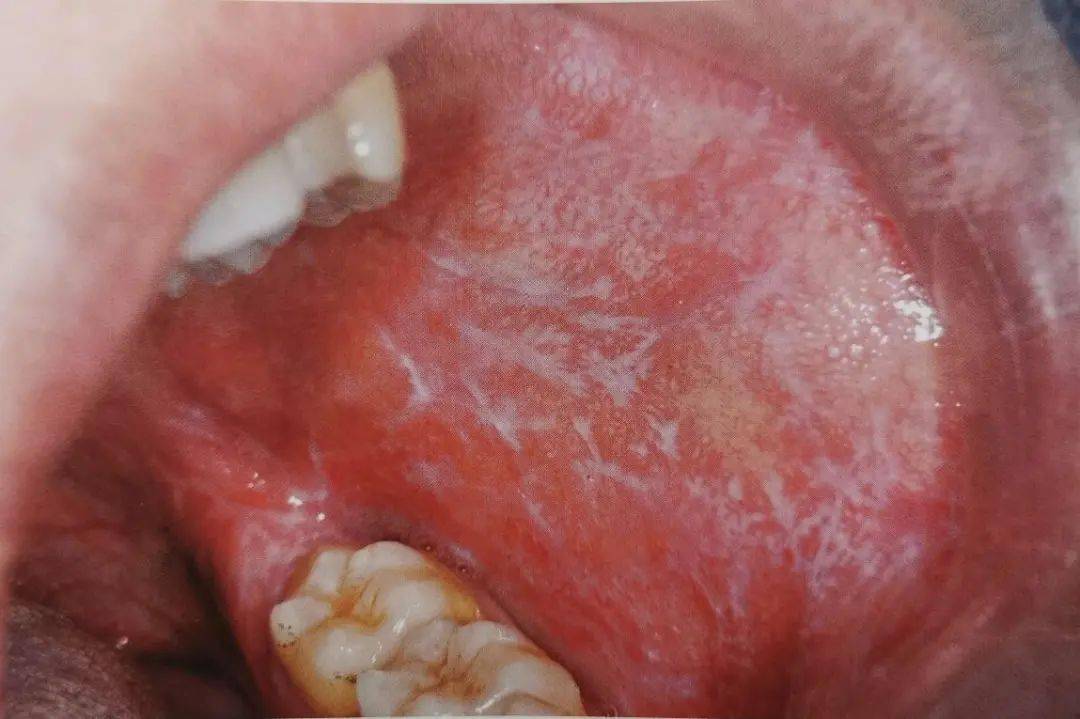

【病例讨论】口腔黏膜溃疡诊断未定,各位帮忙! [病例帖]

口腔黏膜溃疡图片

多图连载(二):口腔黏膜感染性疾病及溃疡类疾病图示